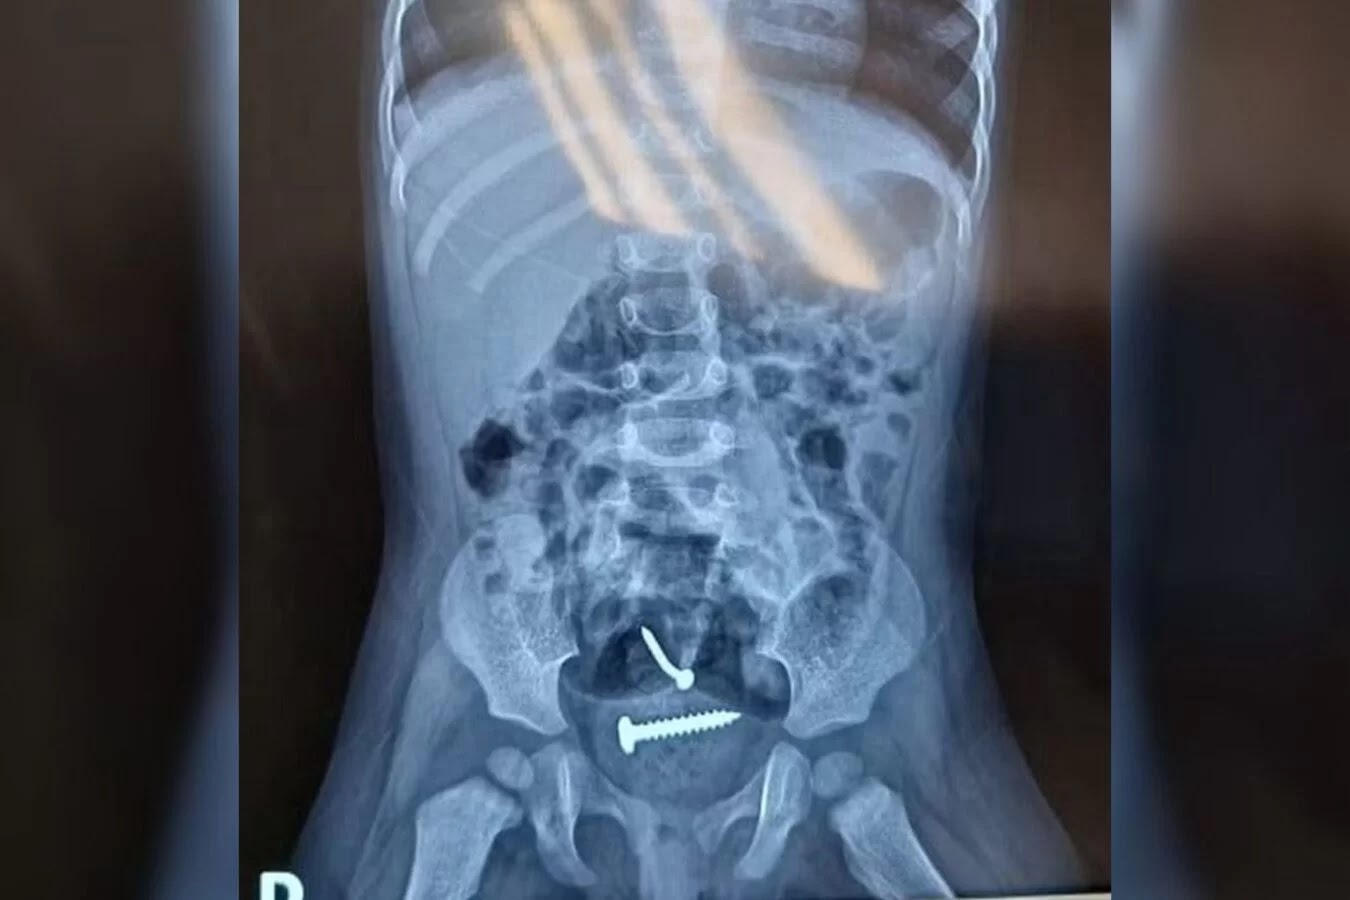

Parafusos no corpo da menina

Elas foram encaminhadas para o hospital e, após a realização dos exames, um raio-X apontou a presença de objetos estranhos dentro do corpo da menina. Ela também tinha lesões nas partes íntimas.